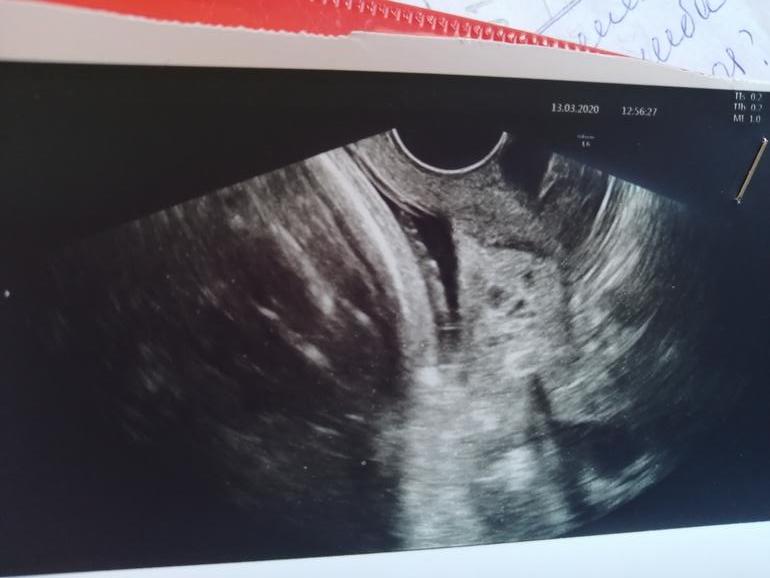

Ну у вас ещё держится 🙏🙏🙏🙏, у вас какой сейчас срок? У меня так то вроде столько времени держалась, а тут по узи смутило внутренний зев что v образный. И не заменили сколько открытие те не видно почему то, хотя всегла видно было ещё и малыш низко лежит.